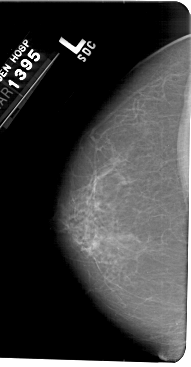

A_1405_1.LEFT_MLO

LEFT_MLO LINES 5491 PIXELS_PER_LINE 3166 BITS_PER_PIXEL 12 RESOLUTION 43.5 NON_OVERLAY